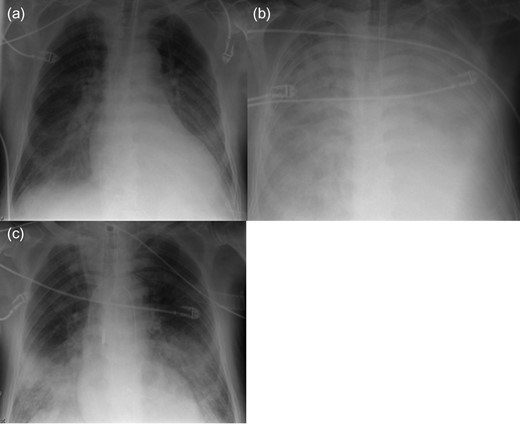

A 66-year-old woman experienced acute dyspnea and was admitted to a regional hospital. Echocardiography revealed severe MR with prolapse of the posterior leaflet. Acute coronary syndrome was ruled out by coronary catheterization. Her condition worsened on Day 2, when she needed a short period of cardiopulmonary resuscitation (CPR). After CPR, the patient was still in severe CS. Therefore, she was transferred to our hospital on the same day. ECLS was immediately implanted percutaneously through the right femoral vessels. Thereafter, her condition stabilized. Ten days after ECLS implantation, surgery including mitral valve replacement, annuloplasty of the tricuspid valve and closure of a giant atrial septum defect was performed. At the operation, an attempt to wean from the ECLS was done, but remained unsuccessful due to right heart failure. After surgery, multi-organ failure (MOF) with massive PE slowly developed (Fig. 2a and b). The Impella system was implanted percutaneously through the left femoral artery on postoperative Day 8 for direct unloading of the LV to treat PE; after implantation, PE showed clear regression on chest radiography (Fig. 2c). Flow from the Impella system was 2.0 l/min, whereas flow from ECLS remained unchanged at 5.5 l/min. Despite her higher systemic output, her general condition had worsened. She died 2 days after Impella implantation due to MOF.

Radiography of Patient 2. (a) After open heart surgery. (b) Before Impella implantation. (c) Two days after Impella implantation.